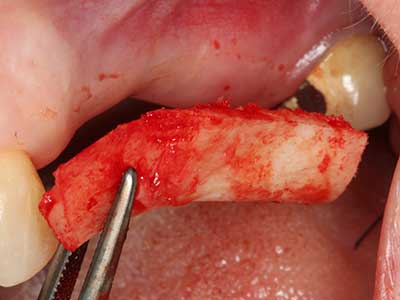

Bei der Knochenblockentnahme zeigen sich weitere Vorteile für die Piezochirurgie: Neben der bereits beschriebenen hohen Präzision bei der Osteotomie stellt sich gerade die Verwendung der dünnen Sägespitzen als besonders materialschonend heraus. Bei der Verwendung insbesondere von Lindemannfräsen sind mit deutlich höheren Entnahmeverlusten durch die dickere Instrumentenspitze zu rechnen (Lakshmiganthan, Gokulanathan et al. 2012). Die insbesondere bei retromolar entnommenen Blocktransplantaten notwendige basale Abtrennung wird durch speziell hierfür vorgesehene rechtwinklige Sägen erleichtert, so dass die Piezochirurgie als präzises, übersichtliches und sicheres Verfahren zur retromolaren Knochenblockgewinnung angesehen wird (Happe 2007) (Abb. 1-12).

Abb. 3: Die basale Abtrennung des Blocks wird durch speziell abgewinkelte Aufsätze erleichtert.